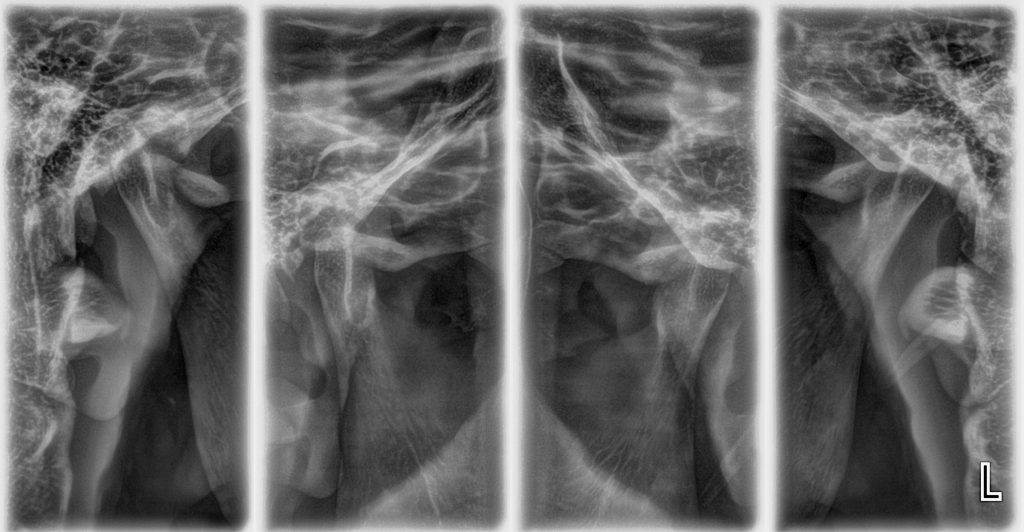

RADIOGRAFÍA Y TOMOGRAFÍA CONE BEAM ODONTOLÓGICA

CRYT Centro Radiológico y Tomográfico Odontológico / Dental en Salta

- Radiología